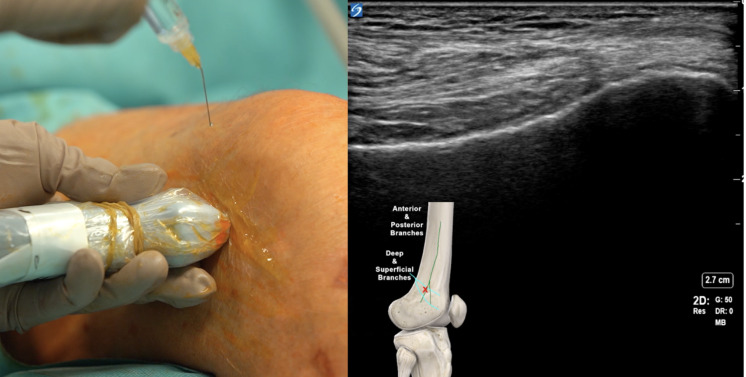

Introduction: Chronic knee pain caused by osteoarthritis (OA) is a prevalent source of disability in the adult population. Total knee arthroplasty (TKA) is an effective surgical treatment for advanced disease, but many patients continue to suffer from chronic post-surgical pain (CPSP). In recent years, minimally invasive techniques targeting peripheral nerves have been explored. Cryoanalgesia of the genicular nerves (GNCryo) is one such intervention that disrupts sensory input by applying extremely low temperatures to the target nerves, potentially leading to sustained pain relief without the need for neurodestructive heat lesions. This study aims to evaluate the effectiveness of ultrasound-guided GNCryo in patients with chronic knee pain due to primary OA or CPSP after TKA.

Methods: This retrospective, single-center study included 90 patients who underwent GNCryo between September 2021 and February 2023. Inclusion criteria were patients over 18 years of age, symptomatic knee OA or CPSP after TKA, and a positive response (≥ 50% pain relief) to diagnostic genicular nerve blocks. Ultrasound guidance was used to optimize needle placement and reduce complications. Clinical outcomes were assessed at baseline and at 1, 3, 6, and 9 months post-procedure. Outcome measures included the Visual Analog Scale (VAS, 0-10) for pain intensity, the Western Ontario and McMaster Universities Arthritis Index (WOMAC, 0-100) for assessing pain, stiffness, and physical function related to OA, the Douleur Neuropathique en 4 Questions (DN4, 0-10) for neuropathic pain, and the EuroQol 5-Dimension (EQ-5D, 0-100) for quality of life.